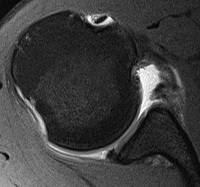

Tendonitis / tendinopathy

Normal

Tendonitis

Tendon thickening / tendinopathy

Sagittal MRI demonstrating severe LHB tendinopathy